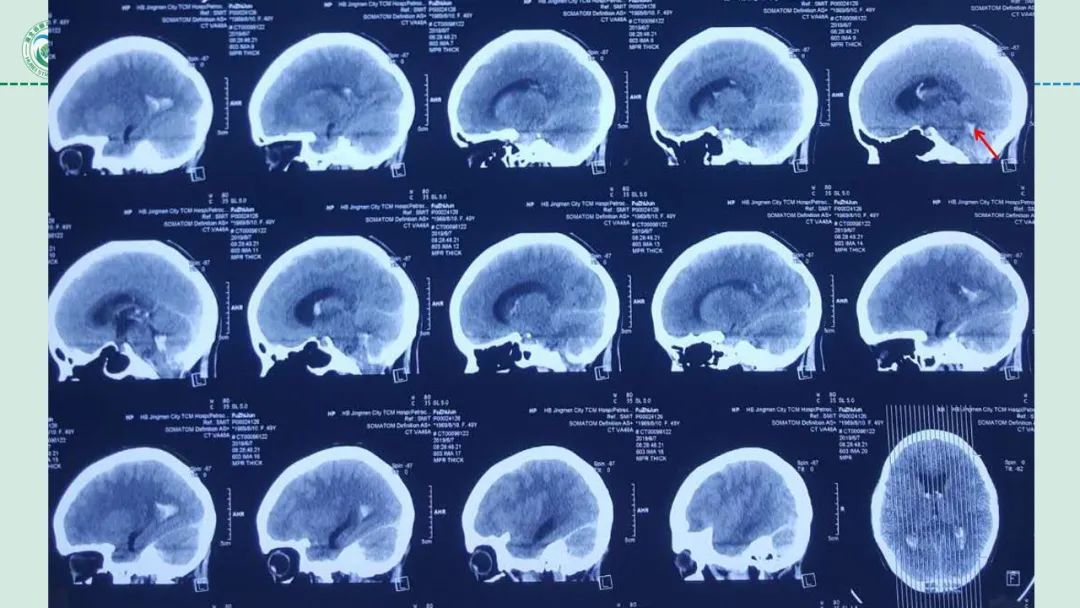

李俊教授团队:右侧PICA延髓扁桃体段多发动脉瘤

今日与大家分享的是《正海-妙术视界》第二百三十二期,由湖北省第三人民医院李俊教授团队带来的右侧PICA延髓扁桃体段多发动脉瘤,欢迎观看、分享。